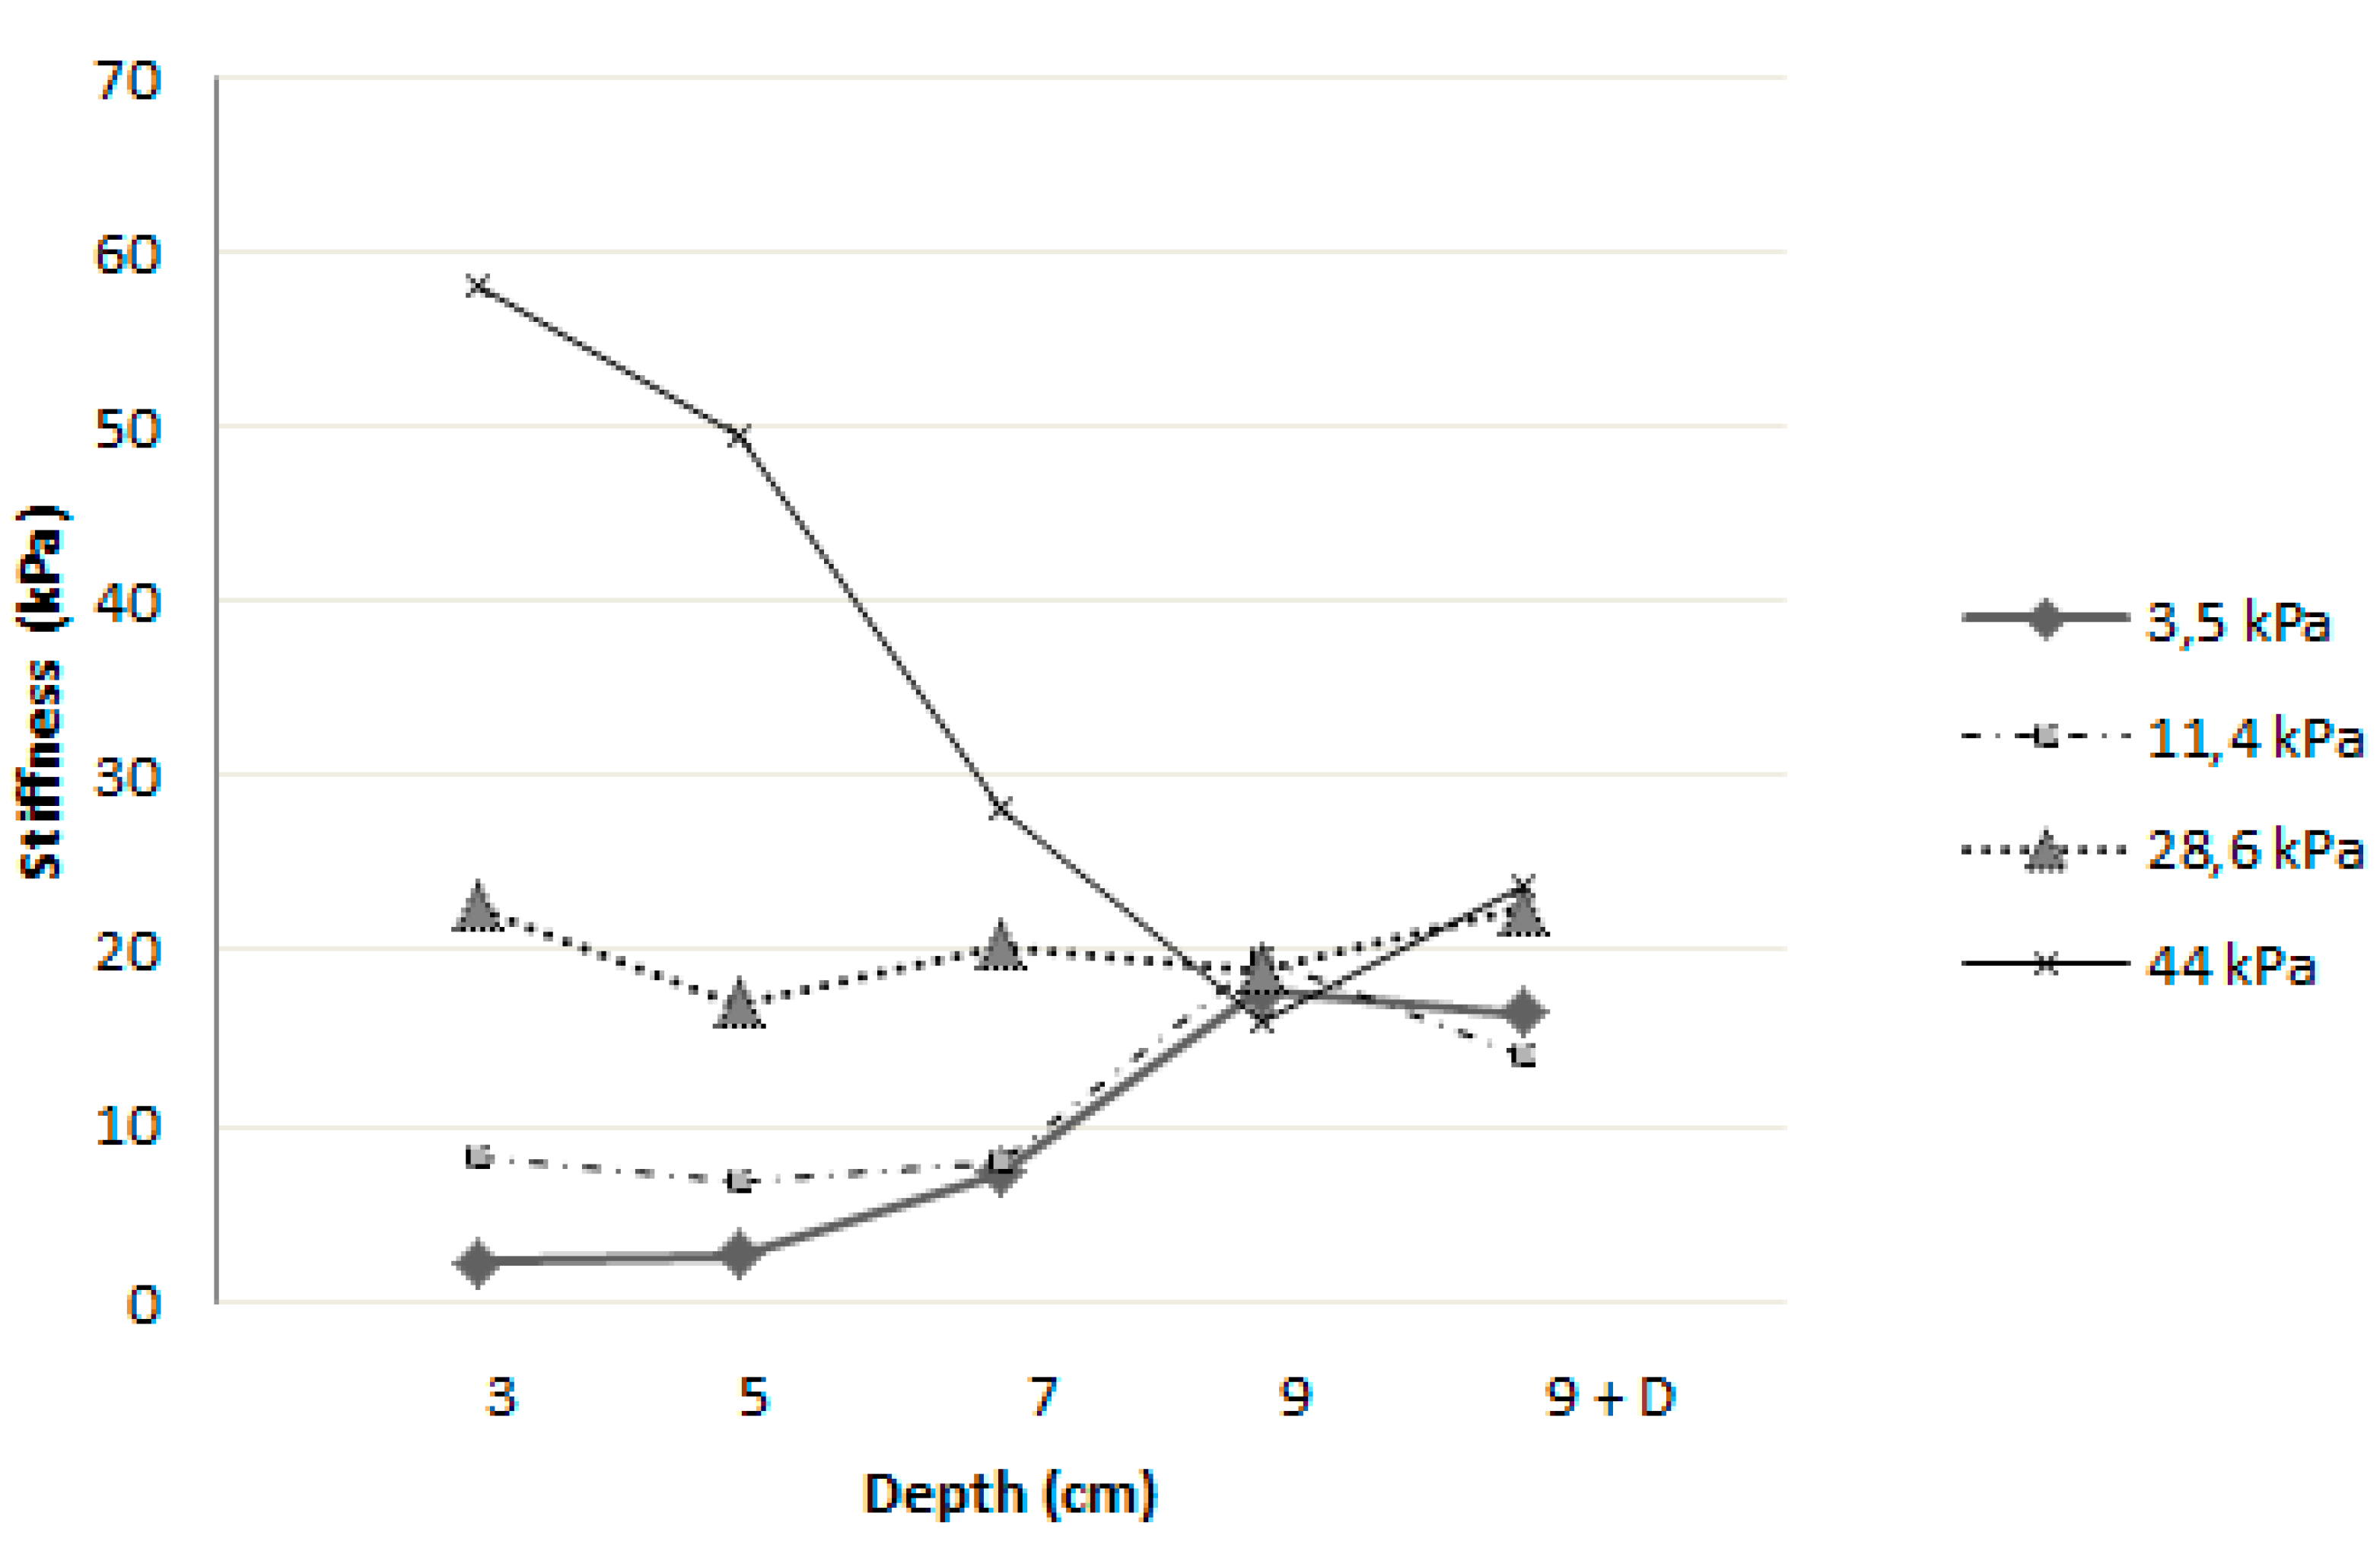

Impact of Depth and Acquisition Protocol on Hepatic Segment Stiffness Measurements

3.2. Influence of Depth on Measured Stiffness

3.3. Robustness of Texture Features in Healthy Livers